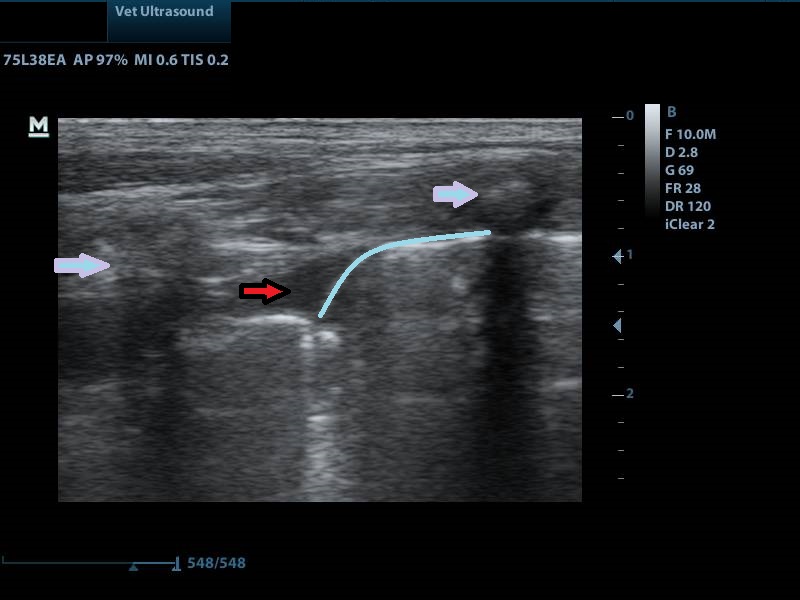

τα βέλη δείχνουν την πορεία των λοβών του πνεύμονα.

μπλε βέλος: ακουστική σκιά από τις πλευρές

κόκκινο βέλος: υγρό

μπλε γραμμή: αφορίζει το πνεύμονα προς τα κάτω